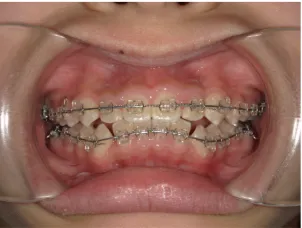

治療中④中1:治療中 マルチブラケット法へ移行

治療後⑤中2:治療終了